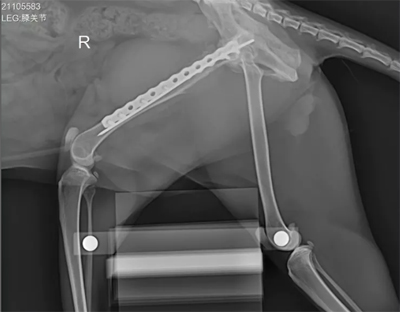

下图这款是华锐生产的 款宠物用X光机,这是 款移动式X射线摄影医疗诊断设备,不仅可以用作宠物X光检查而且也可作为人体X光检查,满足于各类的医疗单位、手术室、宠物医院等场所,请大家根据拍摄的宠物大小来选择合适的机器。